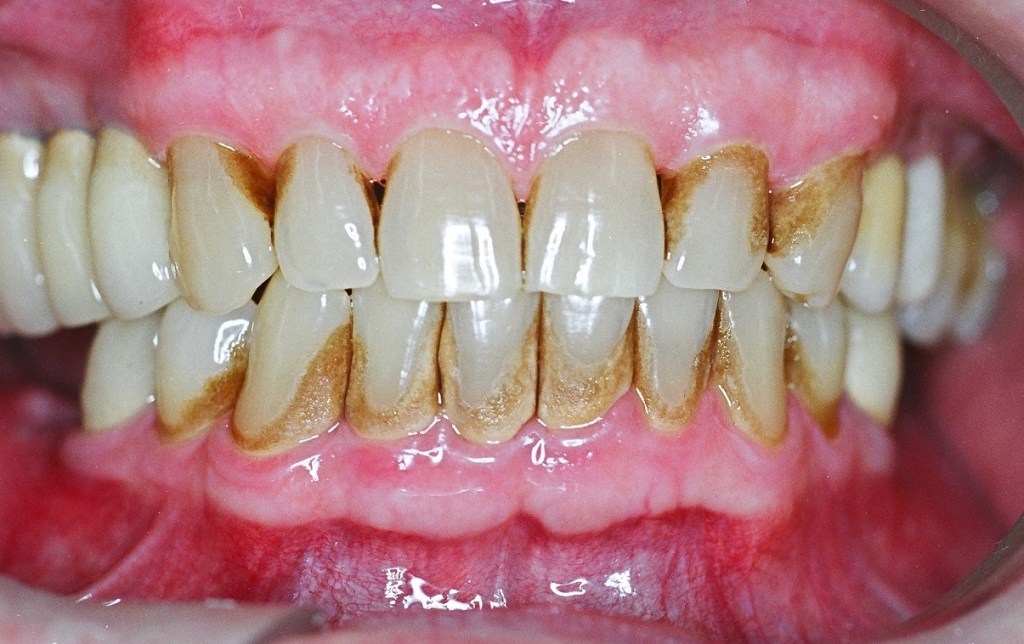

Doenças periodontais

Doenças periodontais assumem uma predominância em pacientes diabéticos devido à interação complexa entre a resposta imunológica comprometida e a inflamação crônica associada à diabetes.

A tendência a inflamações nas estruturas de suporte dos dentes é agravada pela presença persistente de altos níveis de glicose, tornando esses pacientes mais suscetíveis a complicações periodontais.